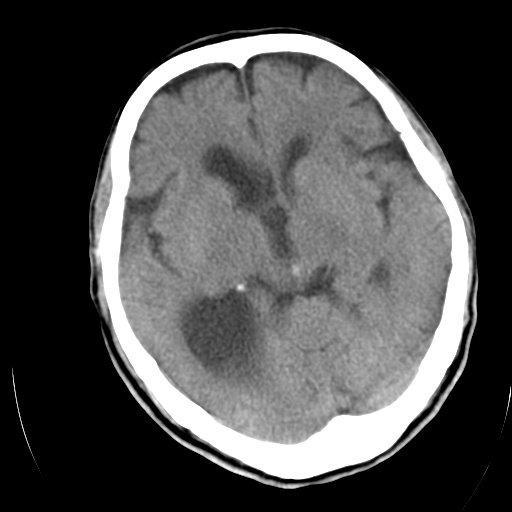

以下是引用泪洒红尘在2009-3-23 19:53:00的发言:[br]第四脑室以上脑室明显扩大,脑沟脑裂无明显增宽加深征象,符合交通性脑积水ct表现。

以下是引用xulianj在2009-3-23 20:31:00的发言:[br]右侧侧脑室扩大,中线结构左移,考虑梗阻性脑积水,建议mri检查。